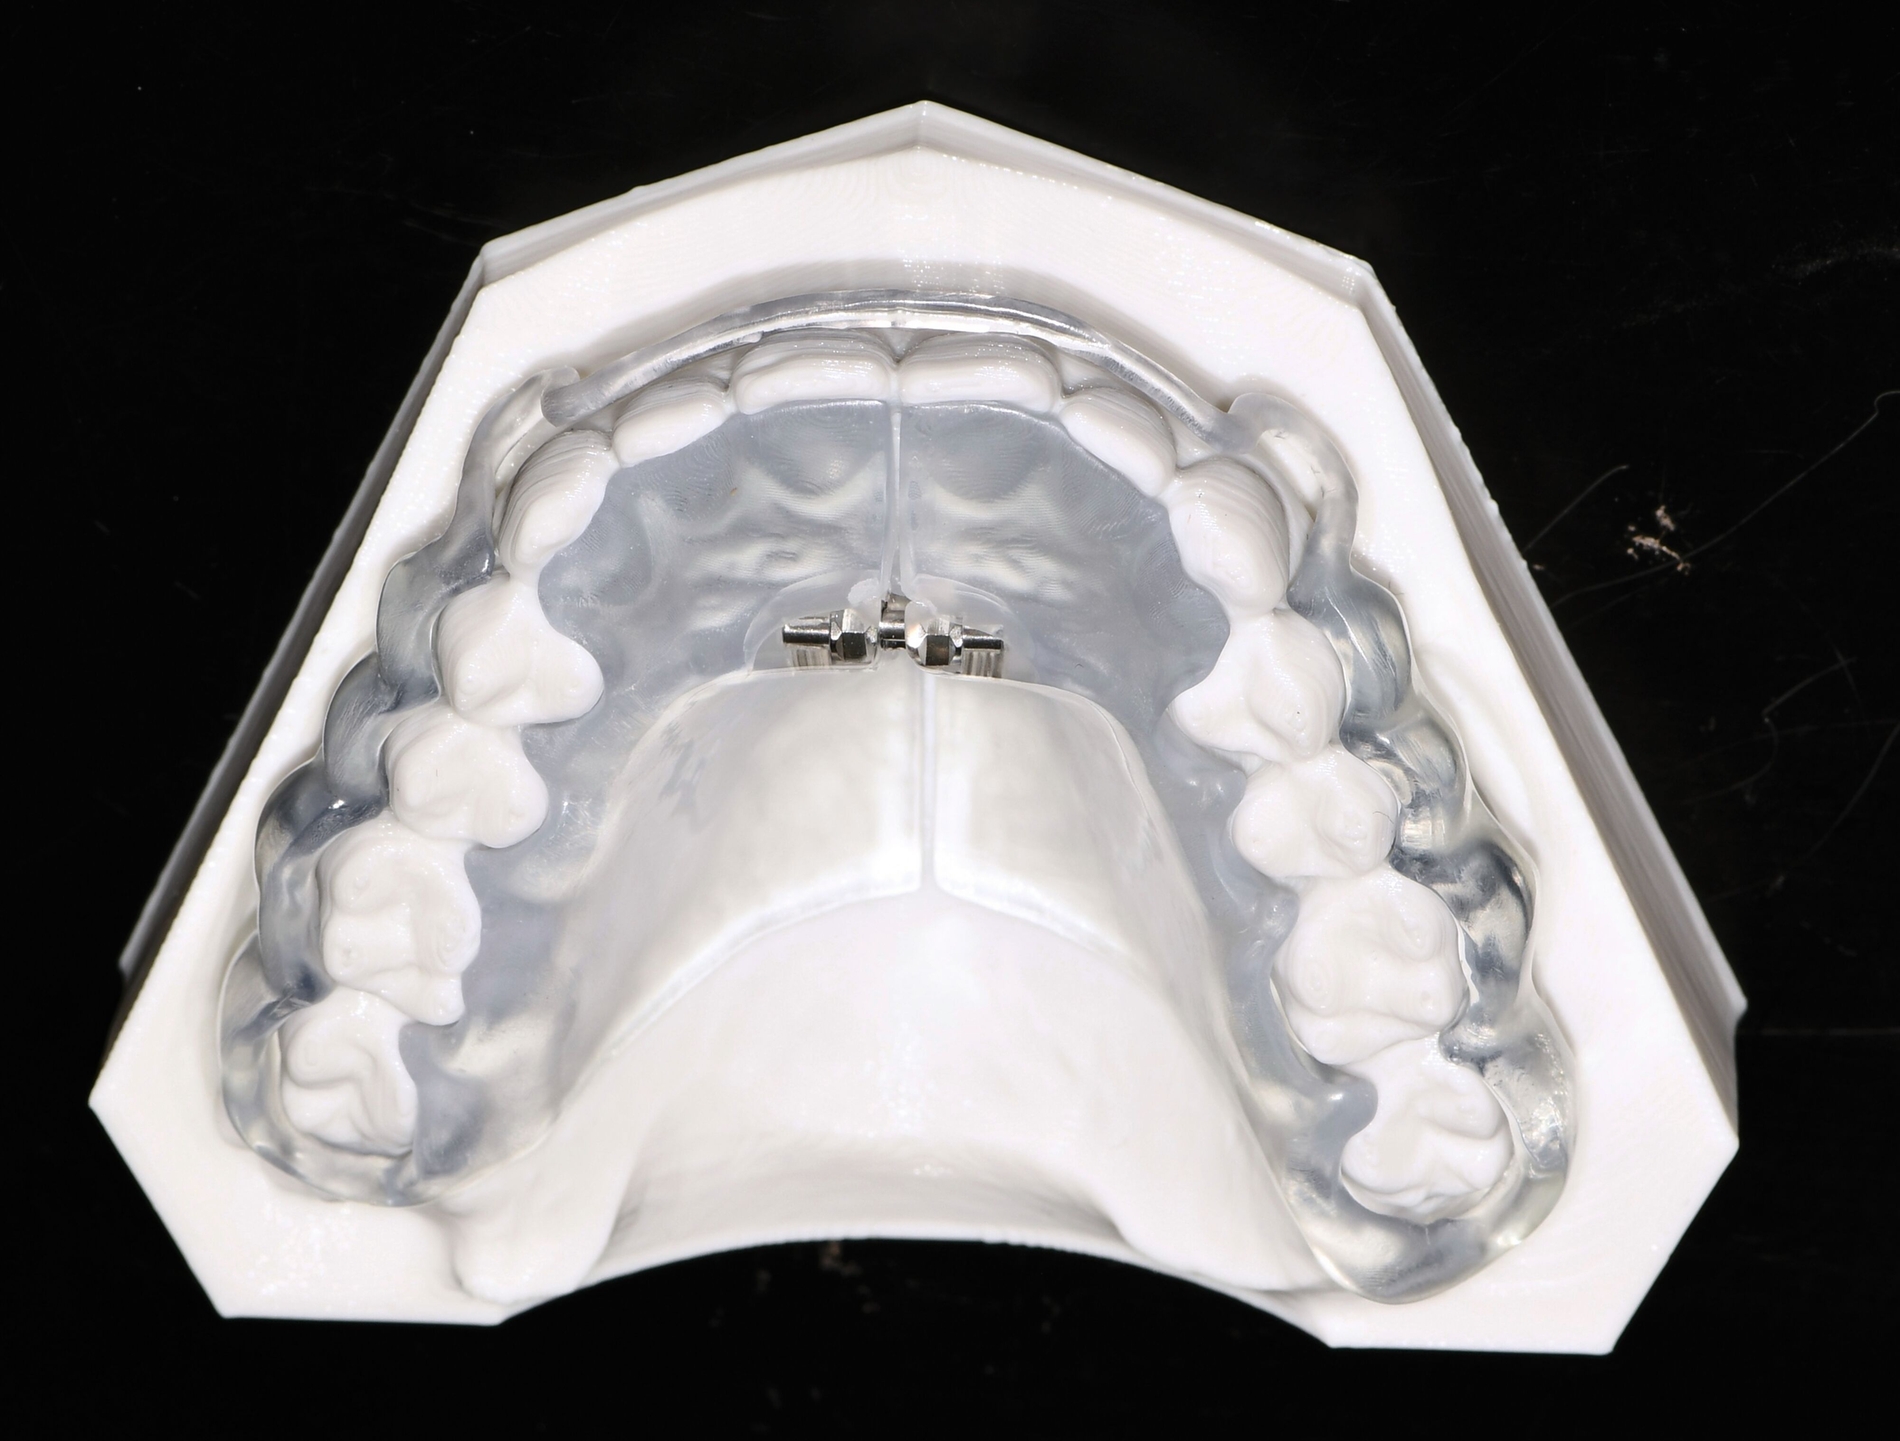

Herausnehmbare Apparaturen

Als hochinnovatives Feld hat sich auch die Herstellung herausnehmbarer Apparaturen im 3-D-Druck entwickelt (Abbildung 4), beschränkt sich jedoch noch auf einzelne Forschungsansätze [Al Mortadi et al., 2012; van der Meer et al., 2016; Graf et al., 2022; Keller et al., 2022]. Intensiv an neuen Konzepten in der Herstellung 3-D-gedruckter herausnehmbarer Apparaturen wird am Universitätsklinikum Heidelberg geforscht. Da herausnehmbare kieferorthopädische Apparaturen im Regelfall bei jungen Patienten eingesetzt werden, kommt dem Vorteil einer unbegrenzten Replikation und einer kostengünstigen und schnelleren Herstellung ein besonderer Stellenwert zu.

Im Unterschied zu konventionellen Apparaturen bestehen die 3-D-gedruckten Apparaturen vollkommen aus Kunststoff. Eine Einarbeitung metallischer Elemente nach dem 3-D-Druck ist möglich [Al Mortadi et al., 2012; Al Mortadi et al., 2024], erfordert jedoch zusätzlichen Zeitaufwand. Zur Herstellung herausnehmbarer Apparaturen eignen sich konventionelle praxisinterne 3-D-Stereolithografie-Drucker, die in vielen Fällen bereits im regulären Praxisalltag zum Modelldruck verwendet werden. Die verwendeten Kunststoffe sollten dabei eine Klasse-IIa-Zertifizierung aufweisen, so dass ein sicherer langfristiger intraoraler Einsatz der Apparatur gewährleistet ist. Weiter muss die Apparatur nach dem 3-D-Druck gemäß den Herstellerangaben nachprozessiert werden. Im Regelfall beinhaltet dieser Prozess ein Waschen in Isopropylalkohol (IPA) sowie eine Nachhärtung im Lichthärtegerät. Eigens durchgeführte Studien sowie die bisherige klinische Erfahrung bestätigen eine hohe mechanische Stabilität, eine hohe Passgenauigkeit sowie eine breite Akzeptanz der Patienten [Roser et al., 2021; Roser et al., 2023; Segnini et al., 2023]. Des Weiteren wecken die 3-D-gedruckten Apparaturen bei den meist jungen Patienten großes Interesse, was wiederum die Trage-Compliance unterstützt. Durch weitere Entwicklungen im 3-D-Druckbereich wird zukünftig auch ein Farbdruck möglich werden.